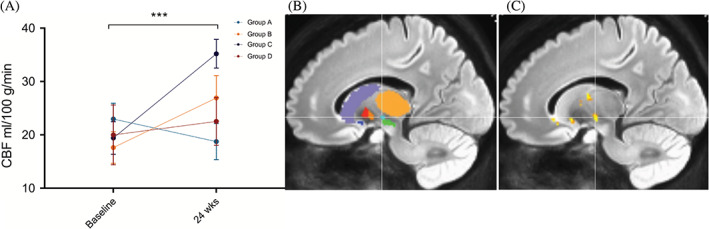

偽連續(xù)動(dòng)脈旋轉(zhuǎn)顯示時(shí)間( P<0.001)和區(qū)域(P<0.001)的主效應(yīng)顯著,但半球( P=0.401)或隊(duì)列(P=0.088)?的主效應(yīng)不顯著。所有基底神經(jīng)節(jié)結(jié)構(gòu)的灌注從基線到輸注后24周總體增加。事后按區(qū)域時(shí)間比較顯示,同種異體hMSC輸注后,隨時(shí)間變化的灌注增加最顯著的是丘腦底核(圖2)。

圖2:灌注變化

圖2